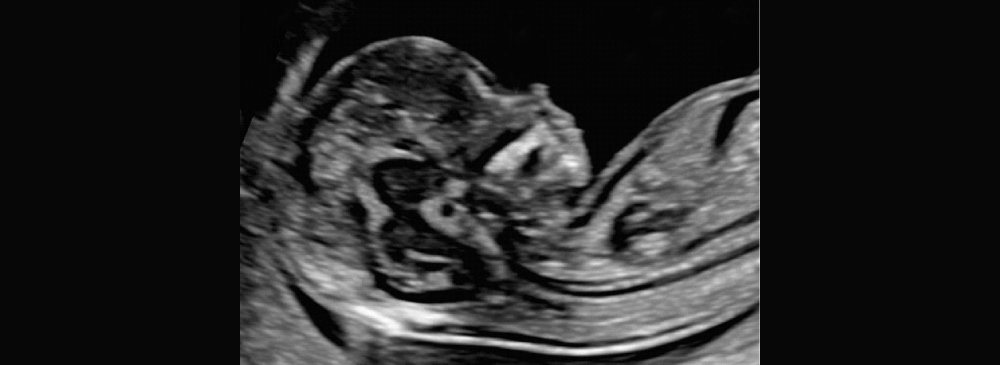

An NT scan, or Nuchal Translucency scan, is a specialized ultrasound that measures the fluid-filled space at the back of your baby’s neck. This scan is typically done between 11 and 14 weeks of pregnancy and forms an important part of the first trimester screening tests. The NT measurement, combined with your blood test and maternal age, helps assess the risk of chromosomal abnormalities such as Down syndrome (Trisomy 21), Edwards syndrome (Trisomy 18), and Patau syndrome (Trisomy 13).

The NT scan is completely safe and non-invasive for both the mother and baby. It offers critical insights into fetal development and identifies potential structural issues early in the pregnancy. Although it does not provide a diagnosis, it helps determine whether further testing, like NIPT or diagnostic procedures, may be needed.

During the NT scan, you’ll lie comfortably on the examination bed while the technician applies gel over your lower abdomen. A transducer (ultrasound probe) is then moved across the abdomen to capture images of the fetus. The radiologist will measure the clear (translucent) space at the back of the baby’s neck, which is the key part of the scan.

In some cases, if the baby’s position does not allow for a clear view, the technician may ask you to shift positions or walk around for a while before retrying. The entire scan typically takes about 20 to 30 minutes and results are usually available the same day or within 24 hours.

- Measures nuchal translucency thickness